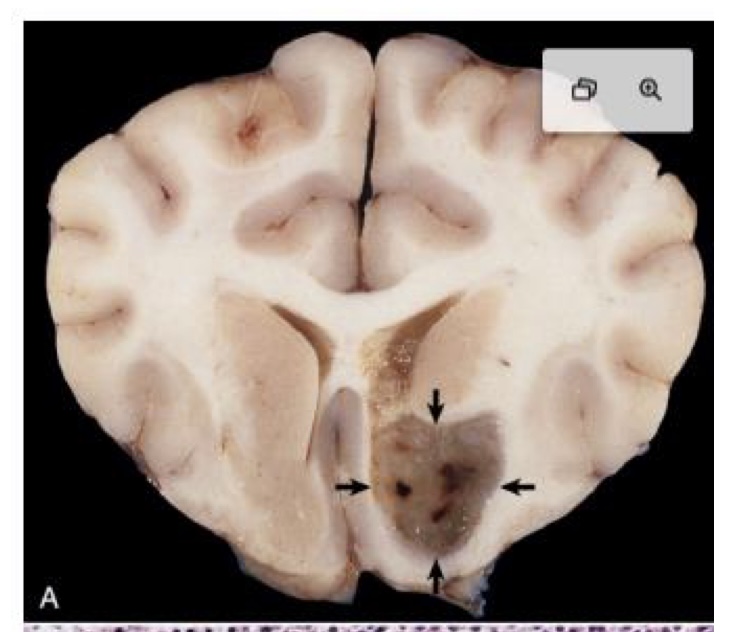

what is this?

oligodendroglioma → tumor is arising in a periventricular location and is gray, soft, and gelatinous